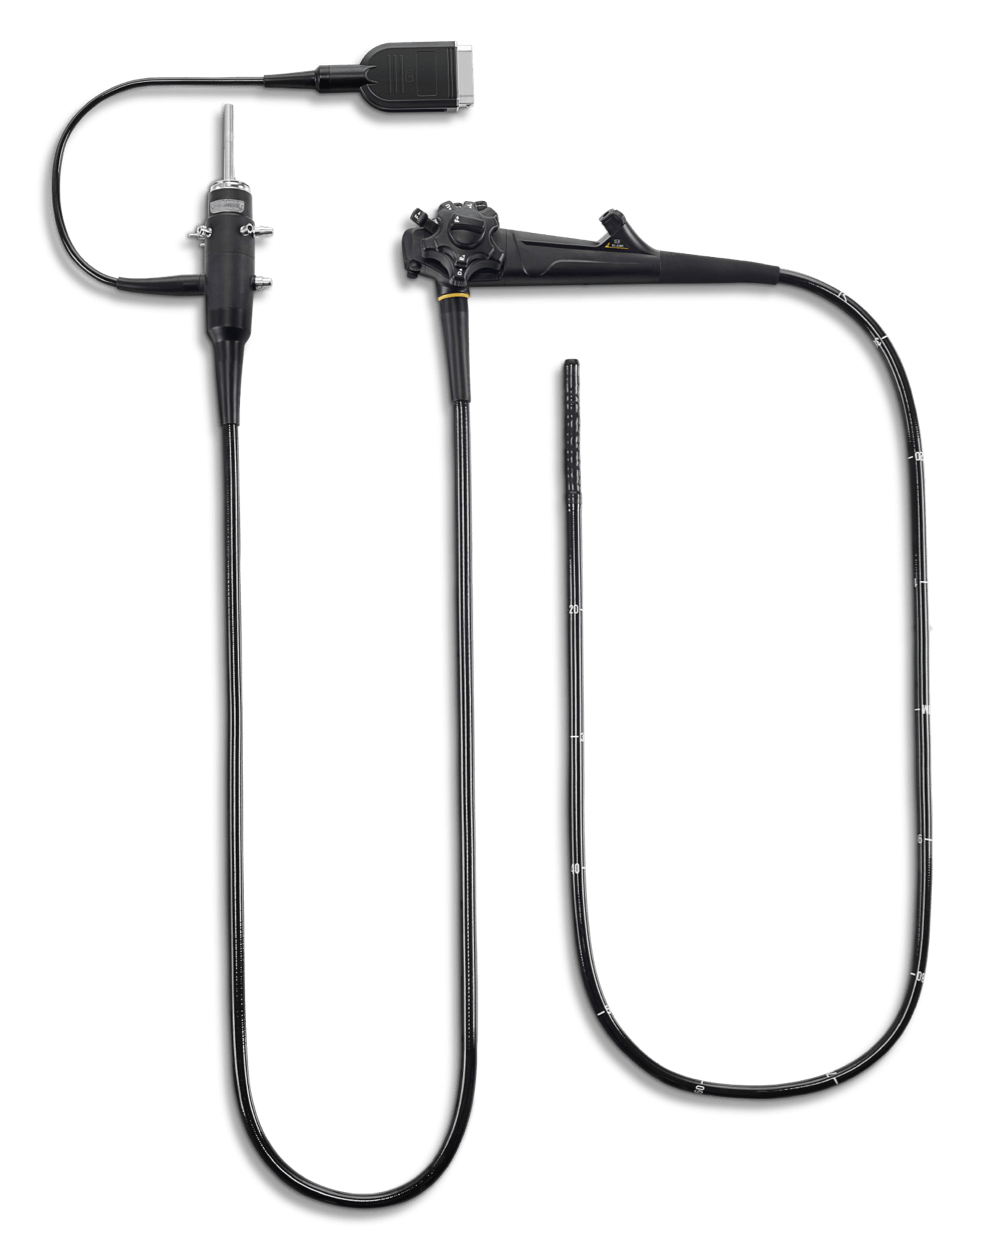

X-2200pro

高清电子内镜系统

高清电子内镜系统

精巧的设计,独具匠心的功能赋予全系列内镜出色的操作体验。 坚持做好每一个细节,只为让您的诊治更加舒心。

全系标配辅助送水功能,可快速冲洗粘膜表面和粘液及出血,发现病变和出血点。

容易抵达一些难以抵达的部位,减少诊疗盲区。

胃镜具有9.3mm的纤细外径。

轻量化手柄,减轻操作者长期持镜的疲劳。

无需断电直接插拔镜体,减少步骤,提升效率,降低镜体损坏风险。

可直接浸泡洗消无需防水帽,避免了因为误操作而导致的进水损坏的风险。

视野方向: 直视(0°)

视场角: 140°

观察景深: 3-100mm

弯曲角度(向上/向下): 210°/90°

弯曲角度(向左/向右): 100°/100°

头端部外径: 9.3mm

插入部主软管外径: 9.3mm

最小器械孔道内径: 2.8mm

有效长度: 1050mm

辅助送水管道: 有

视野方向: 直视 (0°)

视场角: 140°

观察景深: 3-100mm

弯曲角度(向上/向下): 180°/180°

弯曲角度(向左/向右): 160°/160°

头端部外径: 12mm

插入部主软管外径: 12.5mm

最小器械孔道内径: 3.8mm

有效长度: 1350mm

辅助送水管道: 有